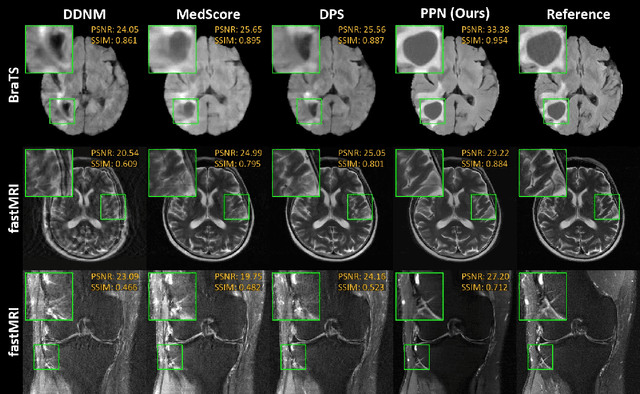

Abstract:Supervised deep learning methods have shown promise in undersampled Magnetic Resonance Imaging (MRI) reconstruction, but their requirement for paired data limits their generalizability to the diverse MRI acquisition parameters. Recently, unsupervised controllable generative diffusion models have been applied to undersampled MRI reconstruction, without paired data or model retraining for different MRI acquisitions. However, diffusion models are generally slow in sampling and state-of-the-art acceleration techniques can lead to sub-optimal results when directly applied to the controllable generation process. This study introduces a new algorithm called Predictor-Projector-Noisor (PPN), which enhances and accelerates controllable generation of diffusion models for undersampled MRI reconstruction. Our results demonstrate that PPN produces high-fidelity MR images that conform to undersampled k-space measurements with significantly shorter reconstruction time than other controllable sampling methods. In addition, the unsupervised PPN accelerated diffusion models are adaptable to different MRI acquisition parameters, making them more practical for clinical use than supervised learning techniques.